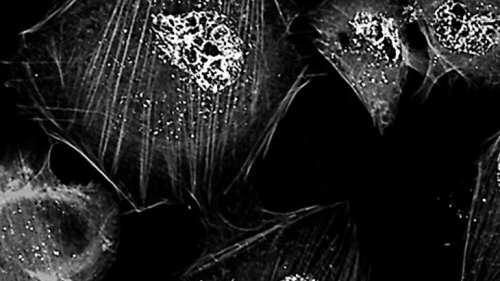

La actividad de las nuevas nanopartículas matando células cancerígenas ha sido investigada por el equipo del doctor Luis Ibarra en su reciente estudio. (Imagen: UNRC / Argentina Investiga)

Los investigadores lograron desarrollar esas nanopartículas y probarlas con éxito en cultivos in vitro de células humanas de glioblastoma.